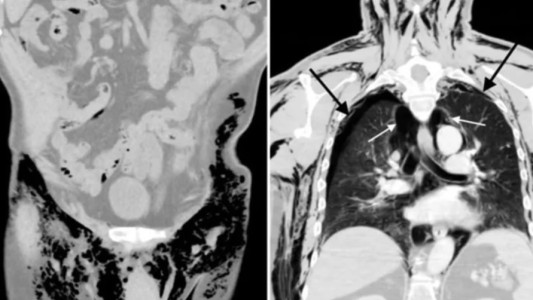

Viruela del mono: la OMS reclamó medidas "urgentes" en Europa para contener la propagación de la enfermedad